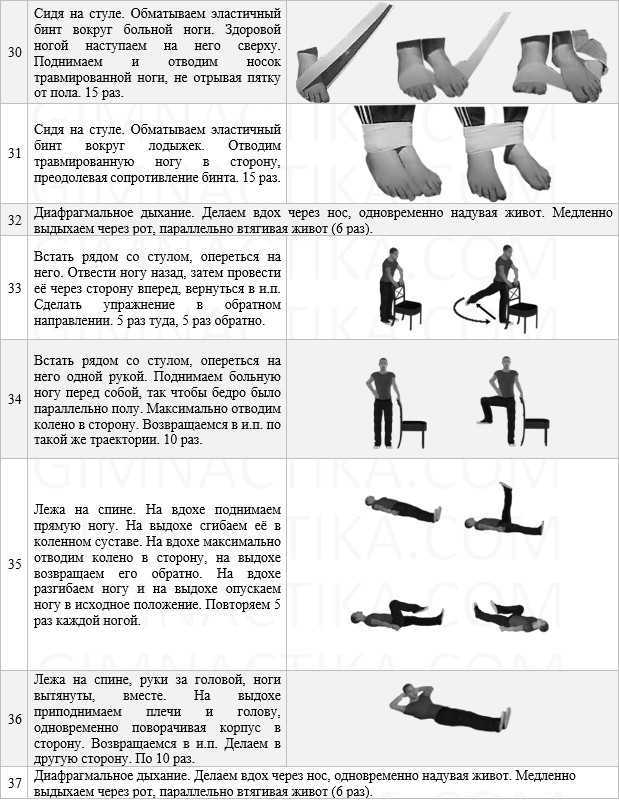

Артроз голеностопного сустава 2 степени схема лечения